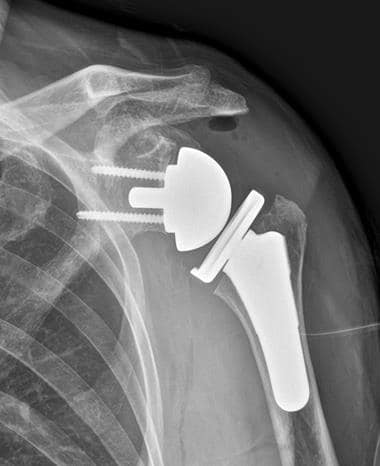

Shoulder Replacement Update, Seoul (South Korea)

Shoulder Replacement Update, Seoul (South

Korea)